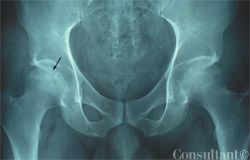

The pattern of pleural calcification and the patient's history are helpful in determining the usually remote cause of the calcification. Here, Drs Mahesh Duggal, Achal Dhupa, Krishna Badhey, and Arunabh of North Shore University Hospital of Forest Hills, NY, offer 2 cases that illustrate the importance of these data.